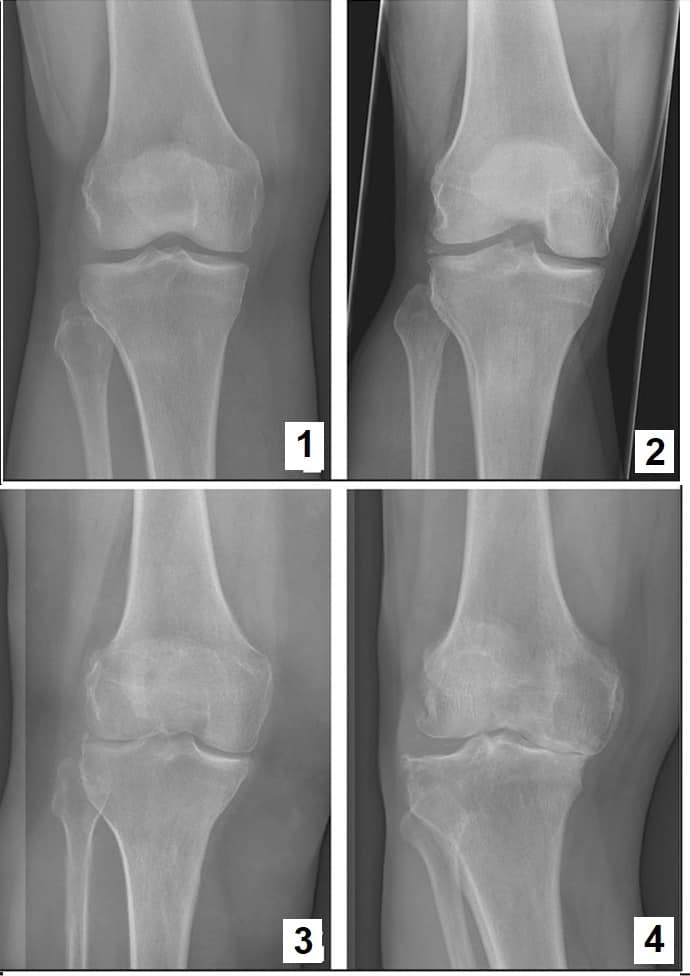

Медицинские снимки: рентген коленного сустава при остеопорозе